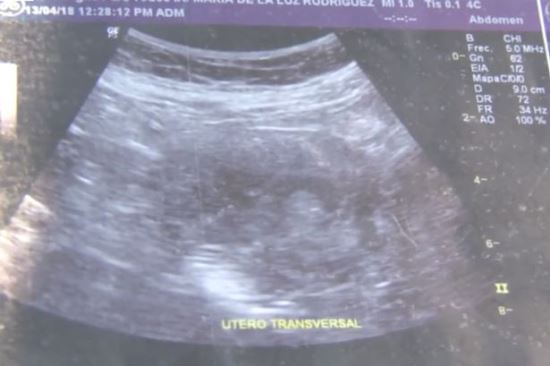

영국 미러 등 외신은 지난 24일(현지시간) 멕시코 시날로아주 마시틀란에 사는 마리아 데 라 루즈(70)의 임신 사실을 보도했다.

보도에 따르면 마리아는 약 7개월 전 다리 통증과 구토, 현기증을 느껴 멕시코의 한 국립 병원을 찾았다.

그는 초음파 검사를 실시했고 임신을 처음 확인했다.

의사들은 첫 검사 결과를 오진으로 판단해 10회에 걸친 재검사를 진행했다.

하지만 모든 검사에서 같은 결과가 나왔고 임신을 최종 확인했다.